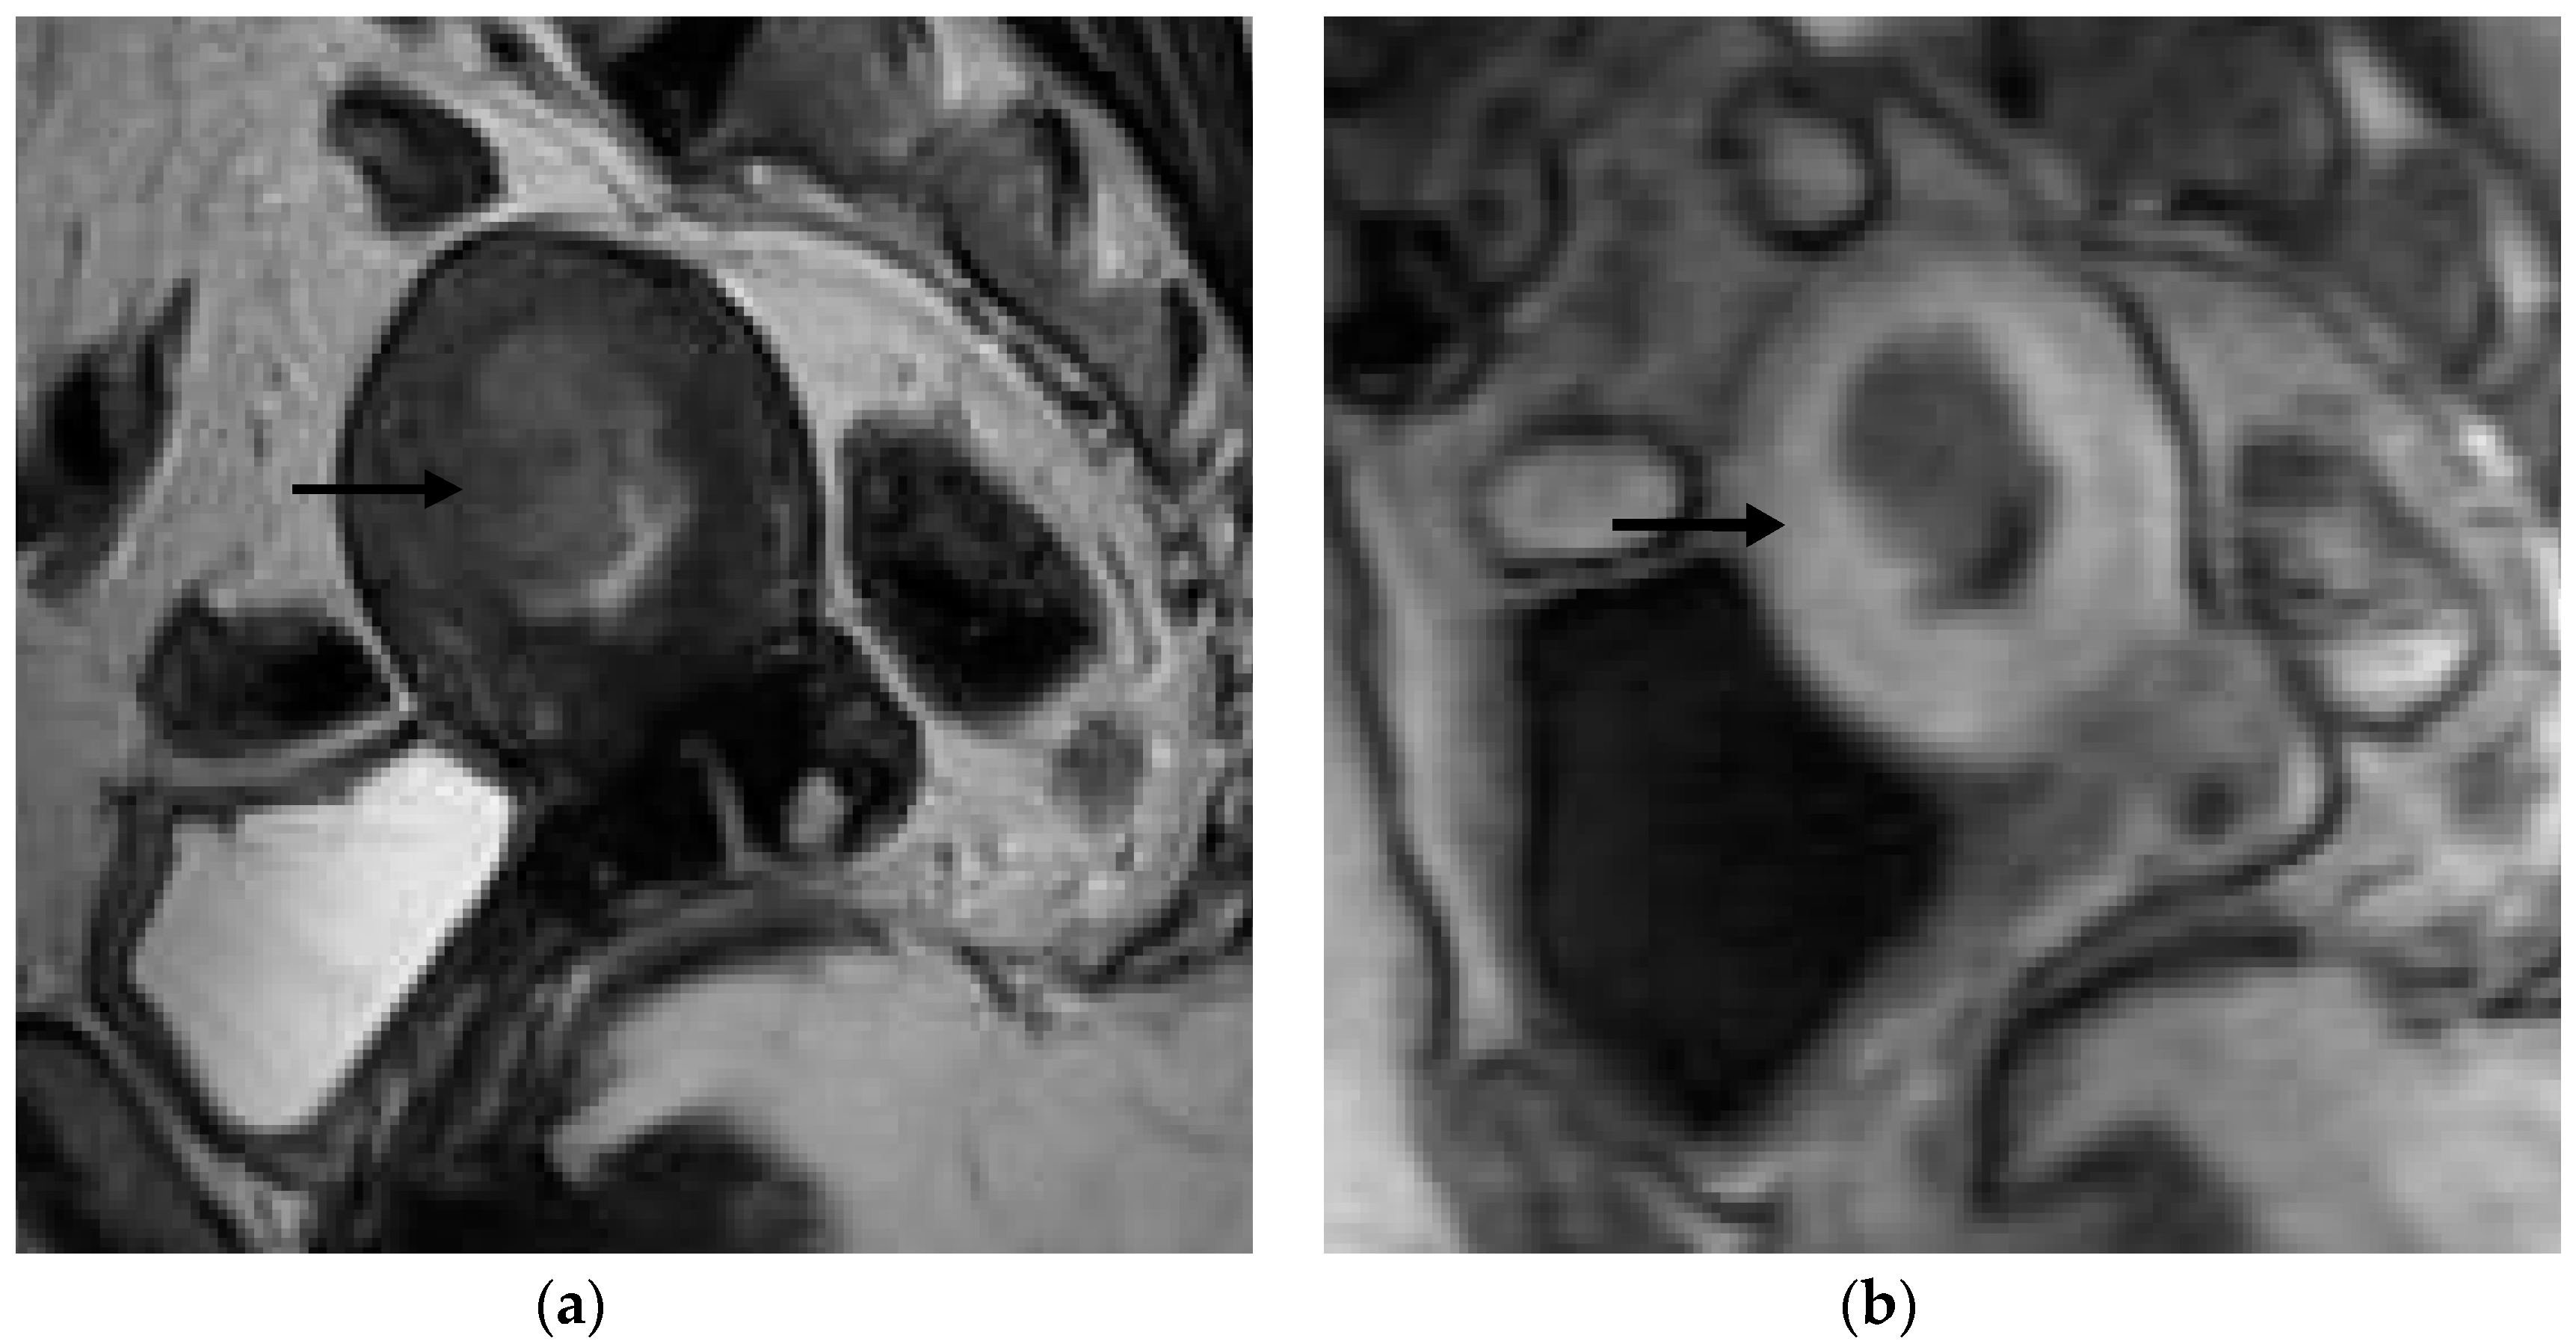

Figure 3. Representative MRI images of endometrial carcinoma of a false-negative case in a 50-year-old postmenopausal woman. (a) Sagittal T2WI MRI image shows a hyperintense lesion with blurring of the junctional zone (arrow). (b) DCE-MRI image shows a hypointense lesion with irregularity of the subendometrial enhancement (arrow) and <50% myometrial invasion. However, the histopathological result revealed ≥50% myometrial invasion.